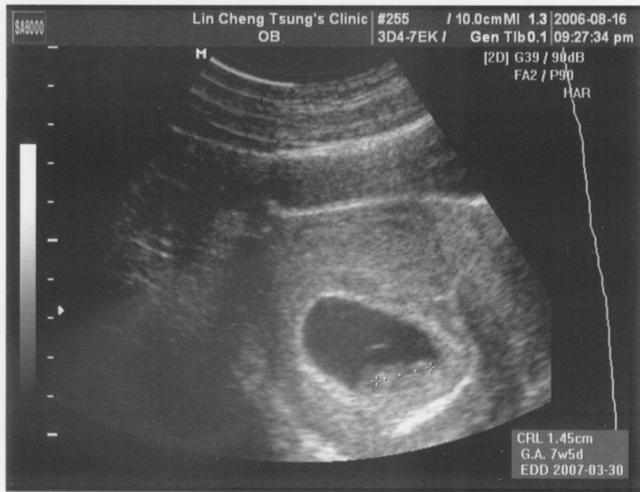

2006.08.16

看著照片感覺很奇妙,越來越奇妙!